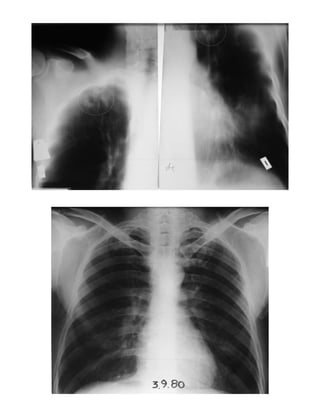

Υγρά Πλευρίτις

Περίπτωση 27η:

Α/Α Φ Η ΤΡΟΠΟΣ ΔΙΑΓΝΩΣΗΣ ΑΚΤΙΝΟΓΡΑΦΙΑ ΑΝΤΙΦΥΜΑΤΙΚΗ ΑΓΩΓΗ ΔΘ ΕΚΒΑΣΗ

27 Α 12

ΠΕΛ ΤΕ ΝΣ

+

+ ++ +++

R

ΙΝΗ

Μ

Z S Νοσ.

Σπ.12

ΙΑ

Ιν.Στ. Υπ.Βλ ΕΠ Θ.

27.α.

27.β.

Φυσιολογική ακτινογραφία σαν επαφή

27.γ.

27.δ.

24-04-89